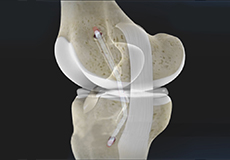

ACL Reconstruction

ACL (anterior cruciate ligament) reconstruction is a commonly performed surgical procedure. With recent advances in arthroscopic surgery, it can now be performed with minimal incision and low complication rates.

Hamstring Autograft

ACL reconstruction with hamstring autograft method is a surgical procedure to replace the torn ACL with part of the hamstring tendon taken from your leg. The goal of ACL reconstruction surgery is to tighten your knee and restore its stability.